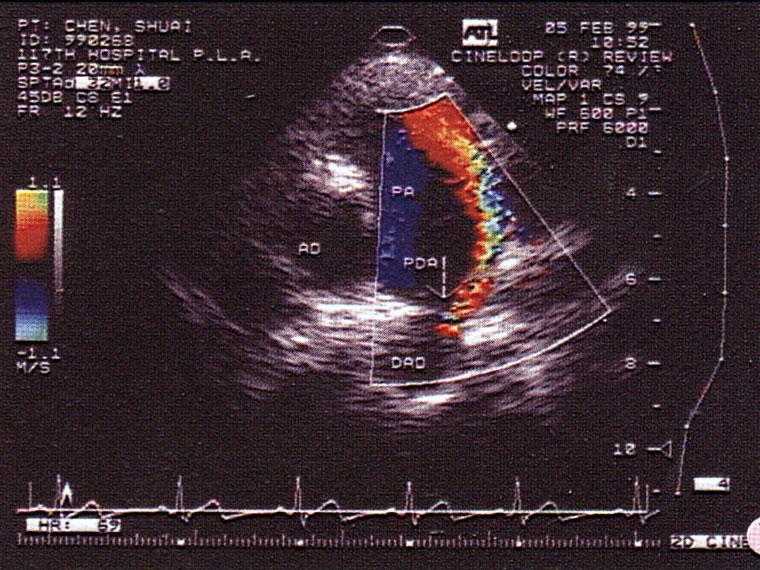

问题 该病例最可能的诊断?(?)

选项 A.主肺动脉间隔缺损 B.动脉导管未闭 C.冠状动脉—肺动脉瘘 D.主动脉窦瘤破裂 E.房间膈缺损

答案 B